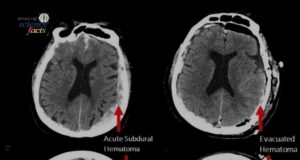

Para saintis telah melaporkan rakaman yang paling luar biasa pernah dirakam di hospital: aktiviti otak daripada seorang pesakit dalam saat-saat terakhir menjelang kematian. Kajian...